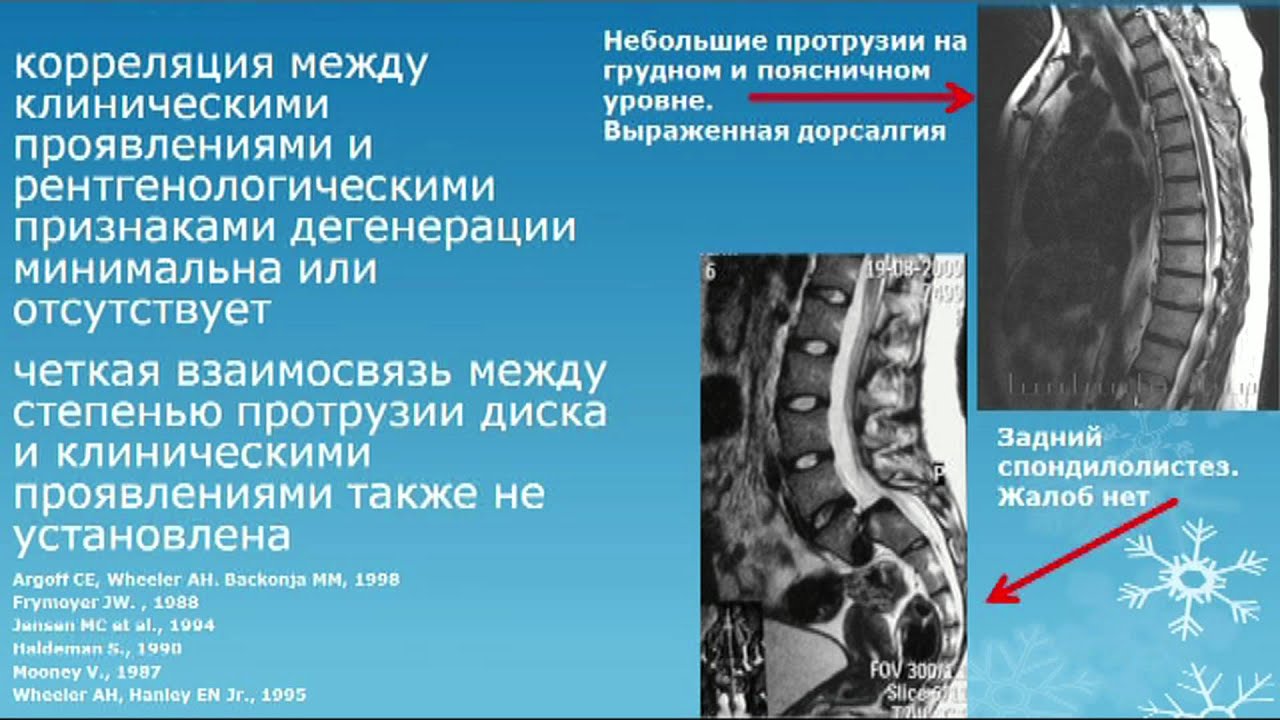

Мрт картина дегенеративно дистрофических изменений пояснично крестцового отдела позвоночника